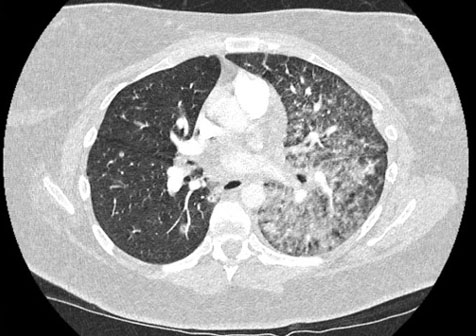

A 35-year-old Caucasian woman developed sudden onset shortness of breath and cough in June 2024, when she was 19 weeks’ gestation in her first pregnancy. Her medical history included well controlled asthma and she had undergone a right partial lobectomy as a child due to a congenital lung defect. She was a never-smoker. She was prescribed a course of oral antibiotics by her general practitioner (GP). Her cough worsened, resulting in her fracturing a rib, at which point she presented to hospital in July 2024 when she was 23 weeks’ gestation. During this hospital admission, she was initially treated for an assumed lower respiratory tract infection with antibiotics (amoxicillin and azithromycin). Routine blood tests showed a WCC 12.2 × 109/L, neutrophil count 9.2 × 109/L, and CRP 52 mg/L, a CXR showed patchy consolidation in left lower zone (Figure 3). She was positive for rhinovirus on a respiratory panel, a screen for atypical lung infections was negative, sputum microscopy culture sensitivities (MCS) negative, COVID negative, negative blood cultures. Despite antibiotics there was no clinical improvement. She went on to have a CT pulmonary angiogram (CTPA) to rule out a pulmonary embolus (PE) as a cause of her ongoing symptoms. The scan confirmed a pulmonary embolus, dense consolidation of her left lung and enlarged mediastinal lymph nodes (Figure 4). A primary lung tumor and tuberculosis were both differential diagnoses. She was commenced on treatment dose low molecular weight heparin and discharged home. Post-discharge her imaging was reviewed in a respiratory radiology meeting and a 2-week wait referral to the tuberculosis team was made.

Figure 4: CTPA done during first admission revealing mediastinal lymphadenopathy and dense consolidation, pulmonary nodularity and interlobular septal thickening in the left lung with nodularity in the right lung.